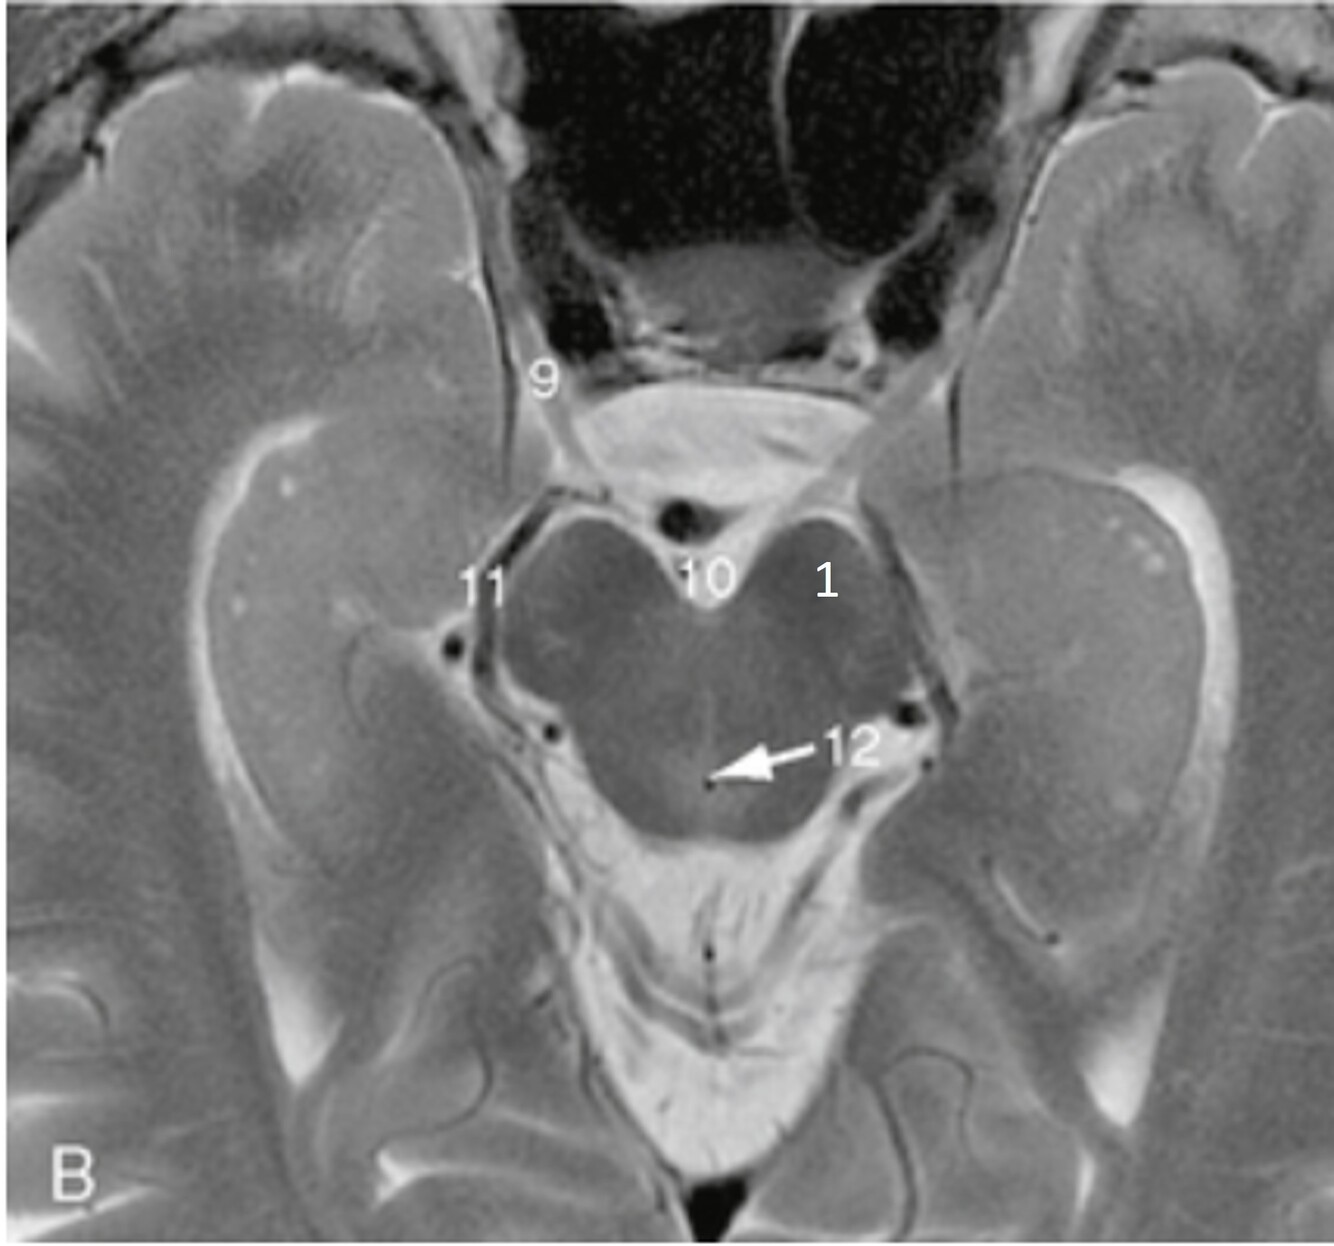

Label 1-6

1=Frontal bone

2-Falx cerebri

3-Left frontal lobe

4-Left anterior cerebral artery

5-Right temporal lobe

6-Temporal horn of left lateral ventricle

Label 7-11

7=Basilar artery

8-Right posterior cerebral artery

9-Internal occipital protuberance

10-Midbrain

11-4th ventricle

Label a,c,d

a=Left cerebral peduncle (of Midbrain)

c=Right ambient cistern (with Rt posterior cerebral artery)

d=Right middle cerebral artery

Label a,b,c,d,f,g

a-Rt lateral fissure

b=Insula

c=Quadrigeminal cistern

d-3rd ventricle

f-Cerebellum

g=Anterior horn (of rt lateral ventricle)

Label a-e

a=Septum pellucidum

b=3rd ventricle

c=Lt Thalamus

d=Genu of corpus callosum

e=Splenium of corpus callosum